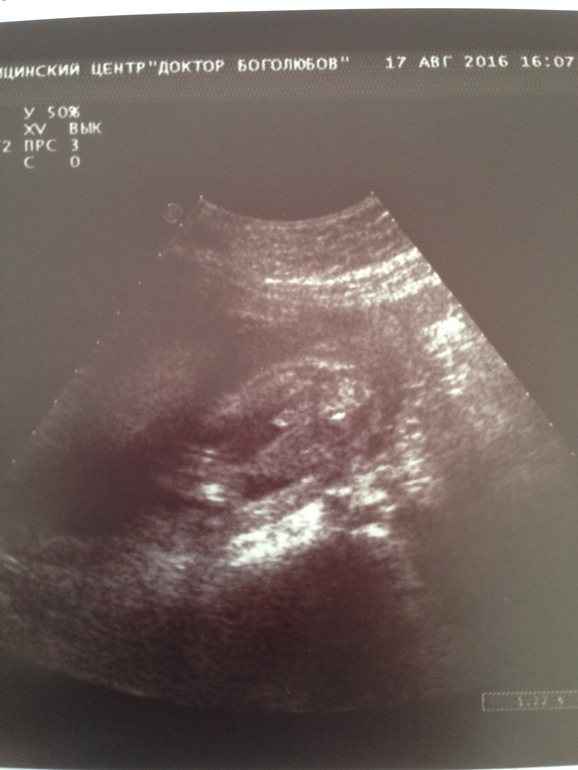

Пол малышаДевочки, привет!! Посмотрите нашу фоточку с УЗИ, пожалуйста! На кого похоже? Врач сказала, что иногда у девочек половые губки такие бывают, потом в норму приходят. В общем, не понятно...)

Думаю мальчик, нам показывали губки нашей девочки, у нее там ничего не торчало и все было понятно